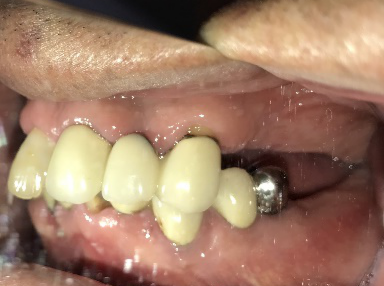

ブリッジの支台になっている奥の歯が、被せ物の中で虫歯になり、支台の役割を果たさず、前方の歯のみで支えられていました。前方の歯をそのままにして、後方の部分を切り離すと、そのまま取れてきました。中は、虫歯で歯根しか残っていない状況でした。この歯は、根管治療後、単独でオールセラミック冠を被せ、歯のないところにインプラントを埋入しました。

After